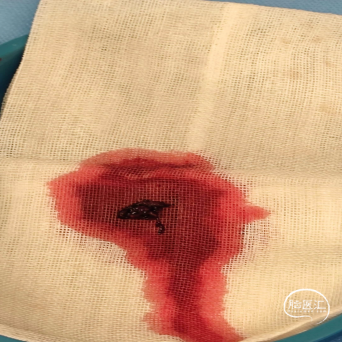

反复抽吸,多次中间管于负压状态下无回血时,负压状态撤出体外,可见大量血栓。